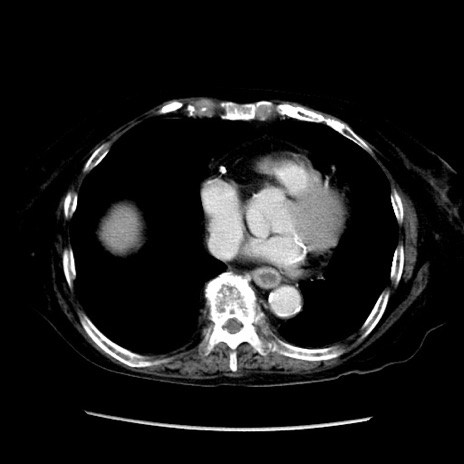

症例14(横断像)

【症例】 90歳代女性

【主訴】 腹痛・嘔吐

【現病歴】今朝から左側腹部痛を認めた。 経過観察していたが、嘔吐を認めたため来院。

【既往歴】 子宮癌術後

【身体所見】 意識清明、BP 127/54mmHg、P 98bpm Sp02 95%(RA)、BT 35.8°C、腹部平坦・軟腸ぜん動音聴取良好、右下腹部圧痛(+) 反跳痛なし

【データ】WBC 9800、CRP 0.46